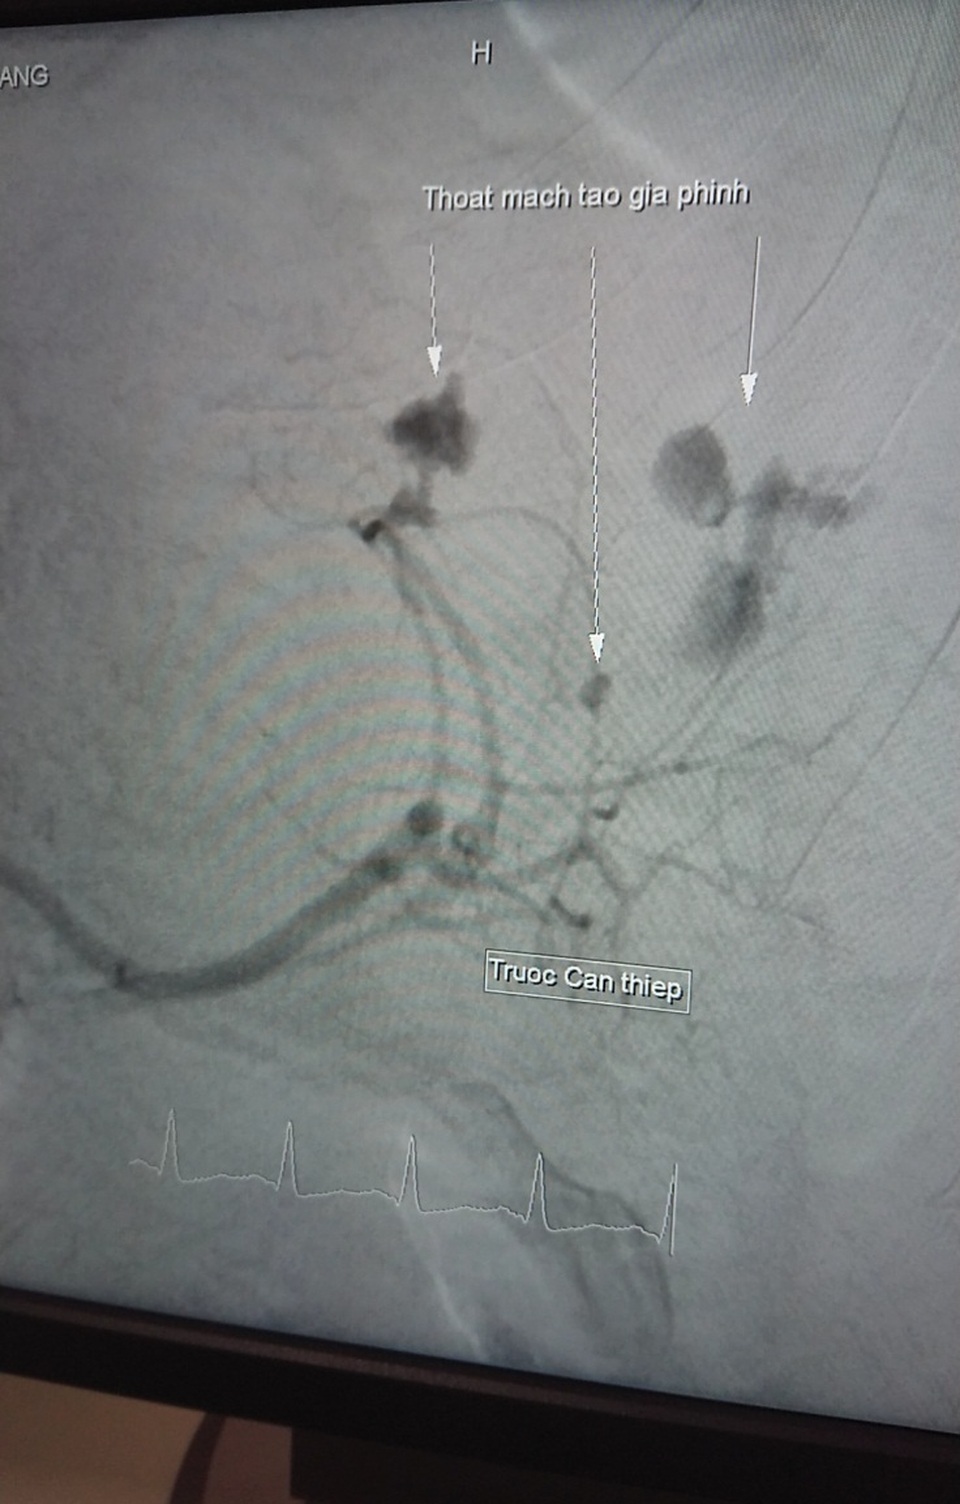

Hình ảnh trước can thiệp nút mạch

Sau khi thăm khám, xét nghiệm, chụp CT Scanner, bác sĩ chẩn đoán, bệnh nhân K. bị vỡ lách độ 3. Ngay lập tức, các bác sĩ hội chẩn và quyết định điều trị bằng phương pháp "nút nhánh động mạch lách đang chảy máu". Đây là phương pháp điều trị nội mạch dưới máy chụp mạch kỹ thuật số xóa nền (DSA). Thủ thuật nút động mạch lách đã được thực hiện thành công trong vòng 30 phút.

Đến sáng ngày 21/5/2019 bệnh nhân tỉnh, tiếp xúc tốt, sinh tồn ổn định, bớt đau bụng. Hình ảnh qua CT Scanner thấy thoát mạch do giả phình động mạch lách đã được tắc hoàn toàn.